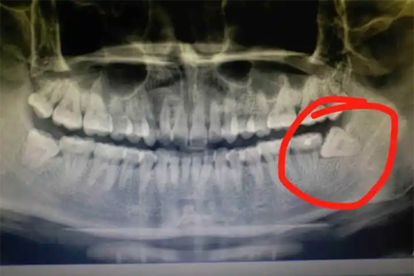

少数情况下智齿完全埋伏于颌骨内,虽无萌出症状但可能压迫神经导致放射性疼痛。若智齿横向生长,可能造成邻牙牙根吸收或颌骨囊肿。阻生智齿易形成盲袋,细菌滋生后会出现剧烈跳痛、化脓及明显口臭,严重时可能引起间隙感染。